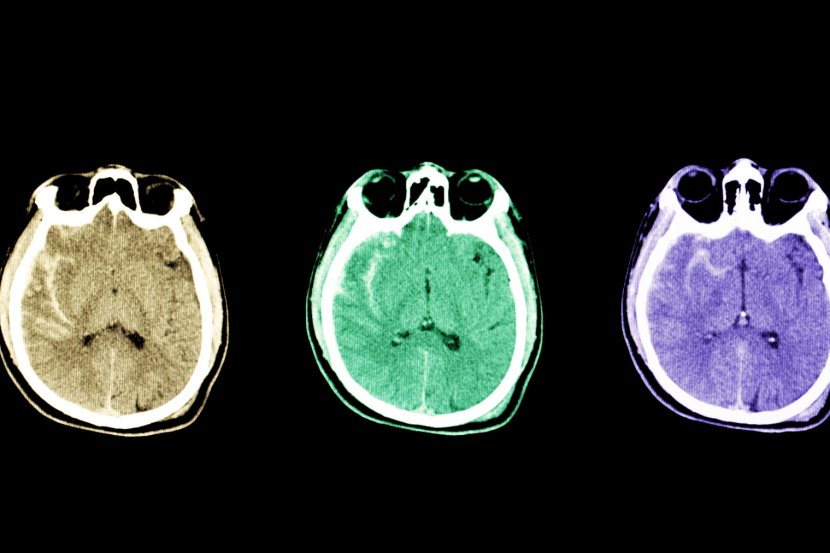

Stručnjaci mogu da dijagnostikuju subarahnoidno krvarenje na osnovu nekoliko dijagnostičkih metoda. Magnetna rezonanca daje detaljan uvid u stanje mozga, moguće je i CT snimanje, angiogram kojim se procenjuje protok krvi kroz krvne sudove. Moguća je i analiza likvora (cerebrospinalne tečnosti) kako bi se utvrdilo moguće prisustvo krvi. Dijagnoza cerebralne aneurizme obično se postavlja tek pošto dođe do subarahnoidalnog krvarenja.